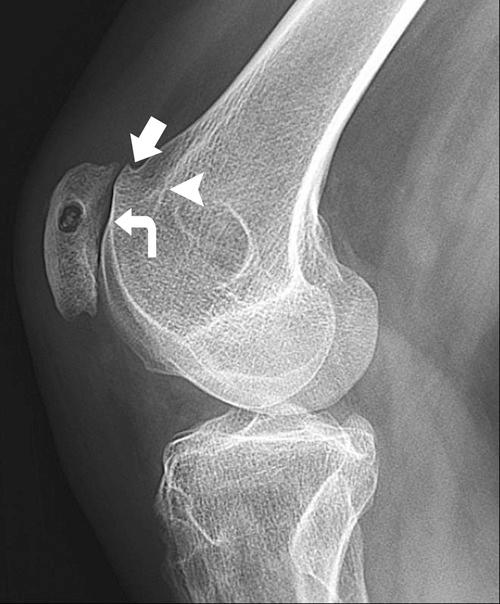

Although disorders of the patellofemoral joint are common in the athlete, their management can be challenging and require a thorough physical examination and radiologic evaluation, including advanced magnetic resonance imaging techniques.

Physical examination and imaging evaluation including standard radiographs are crucial in identifying evidence of malalignment or instability. Magnetic resonance imaging provides valuable information about concomitant soft tissue injuries to the medial stabilizers as well as injuries to the articular cartilage, including chondral shears and osteochondral fractures. Quantitative magnetic resonance imaging assessing the ultrastructure of cartilage has shown high correlation with histology and may be useful for timing surgery.

Evaluation of patellofemoral disorders is complex and requires a comprehensive assessment. Recent advancements in imaging have made possible a more precise evaluation of the individual anatomy of the patient, addressing issues of malalignment, instability, and underlying cartilage damage.